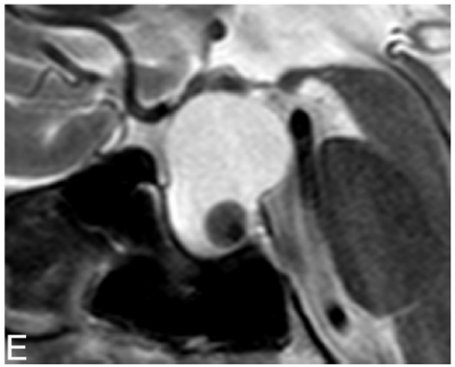

Uma mulher, 50 anos, assintomática, vem à consulta devido a

um achado na ressonância magnética de hipófise. Foi observada

uma imagem intrasselar, hiperintensa em T1 e T2, com nódulo

intracístico, conforme a imagem a seguir: